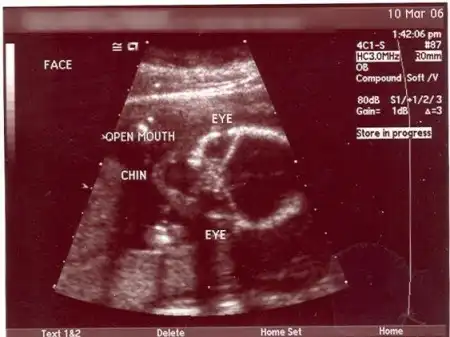

Alien Dad: я чуть не сошел с ума, когда увидел УЗИ своей беременной жены. Я БУДУ ОТЦОМ ИНОПЛАНЕТЯНИНА! Я так горжусь своим пришельцем.